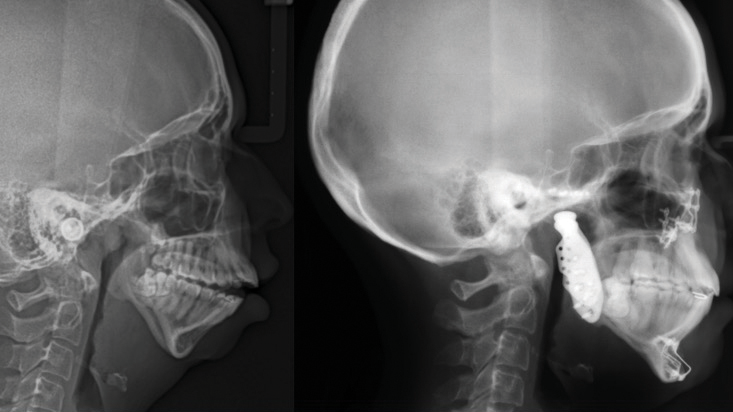

Concomitant Temporomandibular Total Joint Replacement and Orthognathic Surgery

Abstract Facial differences and temporomandibular joint (TMJ) disorders often coexist. Some dentofacial deformities can be a common primary cause of TMJ pathology or develop as a secondary result of joint disease. Patients with these concurrent pathologies benefit from simultaneous surgical management of both issues, typically involving OGS and alloplastic total joint reconstruction (TJR). This article … Read more